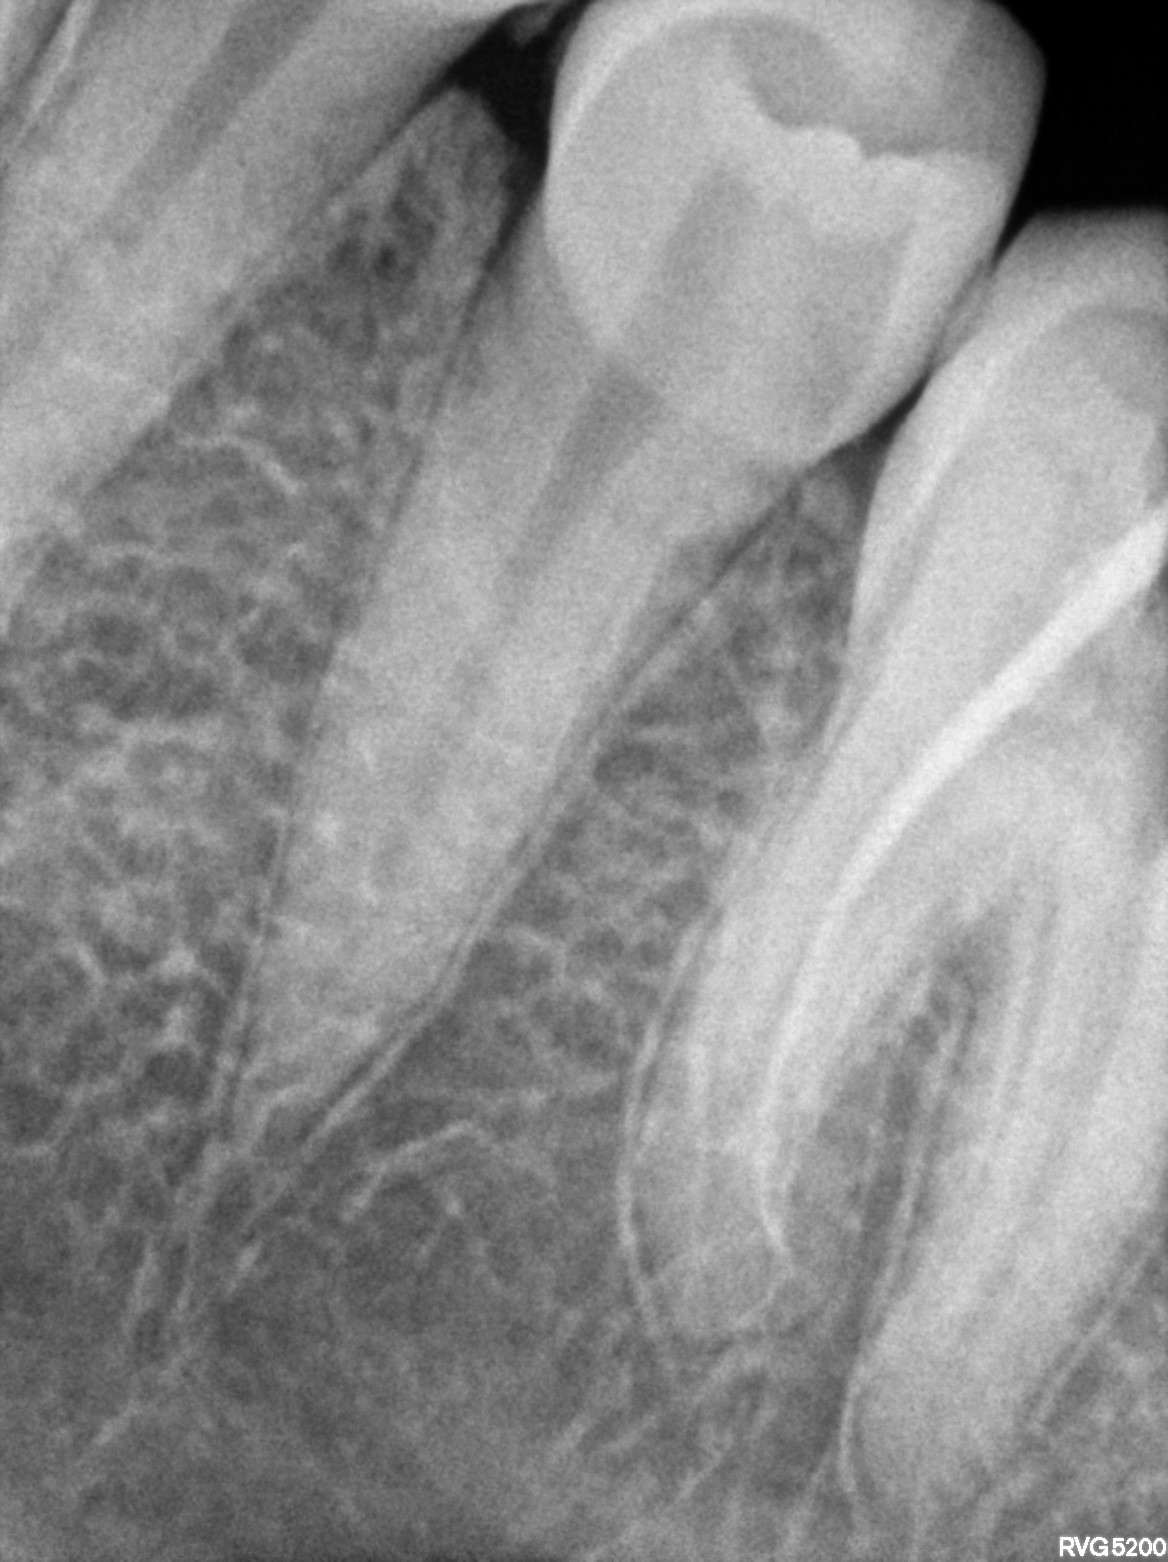

Dental Radiographs FHIR: DocumentReference · LOINC 24641-7

xray_1772782008_2.jpg

24641-7